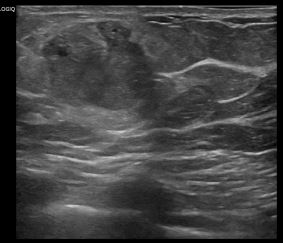

상기환자는 우측유방 만져지는 멍울있어 내원하신 70대 후반

여성분으로 의심스러운 우측유방혹 조직검사 시행해 점액성암으로 진단되었습니다